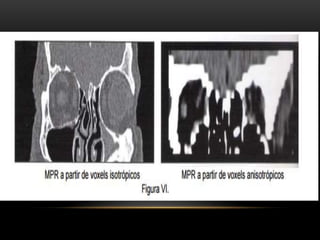

RECONSTRUCCIÓN MULTIPLANAR MPR

• No es reconstrucción tridimensional

• Es una deformación geométrica de los datos.

• Crea una imagen bidimensional con un punto de vista tridimensional

• Las reconstrucciones multiplanares deben de ser calculadas a partir de voxeles isotropicos (

RECONSTRUCCIÓN MULTIPLANAR MPR •No es reconstrucción tridimensional • Es una deformación geométrica de los datos. • Crea una imagen bidimensional con un punto de vista tridimensional

• 51.

• Las reconstruccionesmultiplanares deben de ser calculadas a partir de voxeles isotropicos ( voxel con lados iguales en 3 dimensiones)